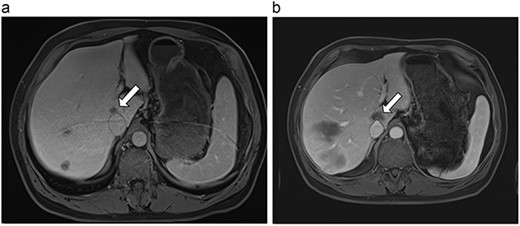

| 3 (5a,b) | 68, F | Colon adenocarcinoma | 6 cycles modified FOLFOX-6 | 8 | Laparoscopic microwave ablation and low anterior resection of colon | 5 | 36.2 | 31.2 | 15 | No |

(a) Pre-ablation MRI demonstrating 5 mm lesion in caudate lobe of liver. (b) Post-ablation MRI (19 days postoperatively) demonstrating 36.2 mm complete ablation of caudate lesion.